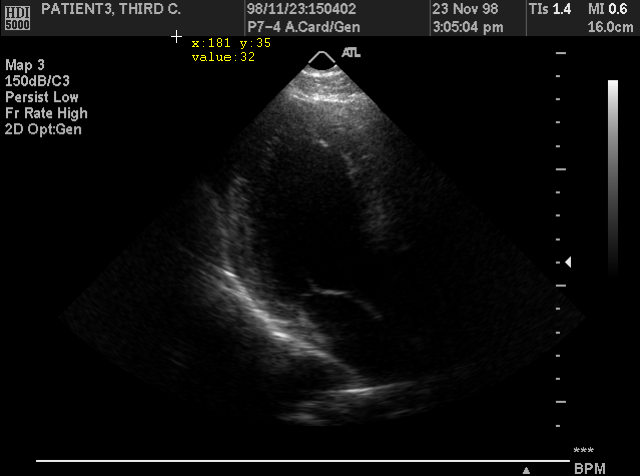

The program has the ability to remove confidential patient data from the header of DICOM files, as well as from the images (e.g. the burned-in names in Ultrasound images). The user can anonymize a single file, a series or study, or all the files within a folder and its sub-folders (batch anonymizing).

Enable this option to allow the program to generate a warning message, when the file's header indicates that there are burned-in annotations on the images, because in this case the header anonymizing is not enough to protect patient information.

Remove burned-in annotations

• Open your DICOM file

• Select the menu command "EditApply To Frame RangeProcessing Actions"

• Select the menu command "ToolsSelectionRectangle"

• Select the area with the patient's name

• Select the menu command "SelectionFill Selected Area", or press the <Shift> + <Delete> keyboard buttons

The program uses the color of the upper-left pixel of the selected area to fill the area.

• Save the file with a different name. The program replaces the pixel data, thus the user has to keep a copy of the original file.